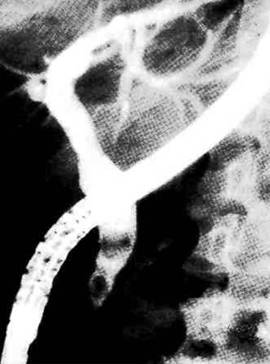

3. назовите метод и опишите его

4. назовите метод и опишите его

5. опишите метод дренирования ВЖП